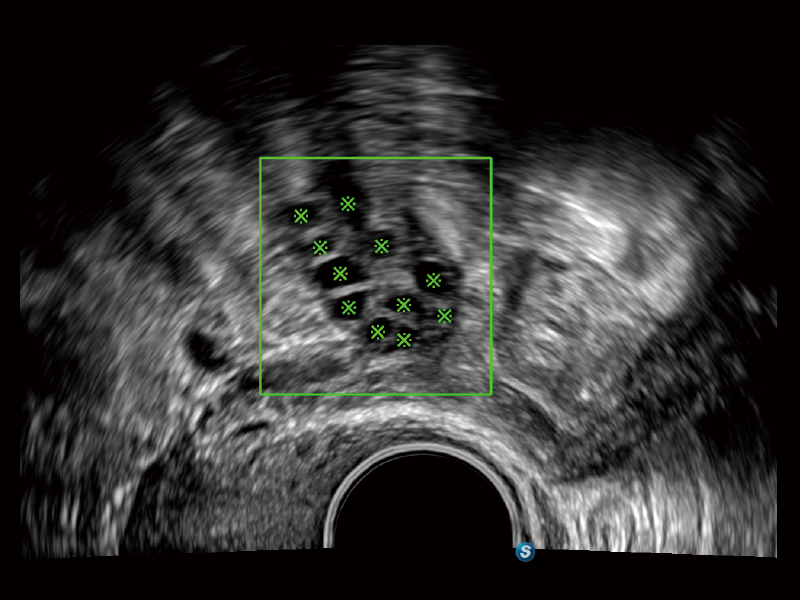

S-Follicle 2D

S-Follicle 3D

S-ERA

HyCoSy with SPI